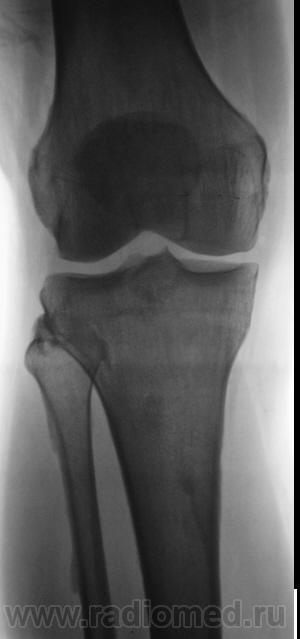

Мужчина средних лет, крепкий, ведущий активный образ жизни, занимающийся дозировано «элементами спорта», полковник милиции, в последнее время (несколько лет) почувствовал боли в области правого коленного сустава.

Снимки ниже.

Просьба высказать мнения по представленным иллюстрациям.

Энтезопатия надколенника, перегрузочная болезнь б/б кости(подозрение на неполный перелом).

Очень похожая картина на консолидированный перелом б\б кости. В проекции м\б кости определяется периостальная реакция или патологическая перестройка костной ткани.

Есть  признаки  артроза  и  синовита . Была  повреждена  передняя  крестообразная  связка.